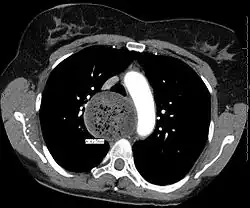

An axial CT image showing marked dilatation of the esophagus in a person with achalasia.

Due to the similarity of symptoms, achalasia can be mistaken for more common disorders such as gastroesophageal reflux disease (GERD), hiatus hernia, and even psychosomatic disorders. Specific tests for achalasia are barium swallow and esophageal manometry. In addition, endoscopy of the esophagus, stomach, and duodenum (esophagogastroduodenoscopy or EGD), with or without endoscopic ultrasound, is typically performed to rule out the possibility of cancer.[11] The internal tissue of the esophagus generally appears normal in endoscopy, although a "pop" may be observed as the scope is passed through the non-relaxing lower esophageal sphincter with some difficulty, and food debris may be found above the LES.